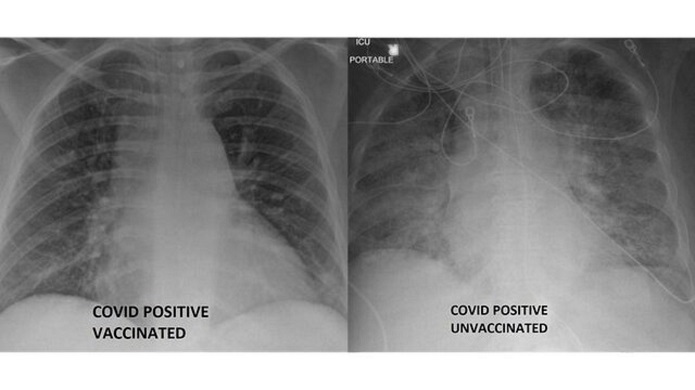

در همین رابطه دو تصویر عکسبرداری که سازمان سلامت اساسام تهیه کرده و هر دو تصویر از افراد مبتلا، اما یکی متعلق به فرد واکسینه شده و دیگری مربوط به فردی است که واکسینه نشده، تفاوت اثر ویروس بر ریه افرادی را نشان میدهد از لحاظ واکسیناسیون شرایط متفاوتی دارند.

دکتر کامل در این باره گفت: سفیدی که در ریه افراد واکسینهنشده دیده میشود آسیب ناشی از ویروس است. این میتواند باکتری، مخاط یا ترشحات باشد.

به گفته این پزشک، بیماران واکسینهنشدهای که ریه آنها در این تصاویر عکسبرداری مشاهده میشود به احتمال زیاد به مراقبت قابلتوجهی نیازمندند.

دکتر کامل گفت: آنها بیتردید دستکم به اکسیژن نیاز دارند و اغلب به اکسیژن بیشتری نیاز دارند. شاید به دستگاه تنفس مصنوعی یا لولهگذاری برای هوارسانی با دستگاه، آرامبخش و مراقبت علایم حیاتی نیاز داشته باشند.

او در ادامه افزود ریههای سالم و پر از هوا در تصاویر عکسبرداری نواحی سیاه بیشتری دارند.